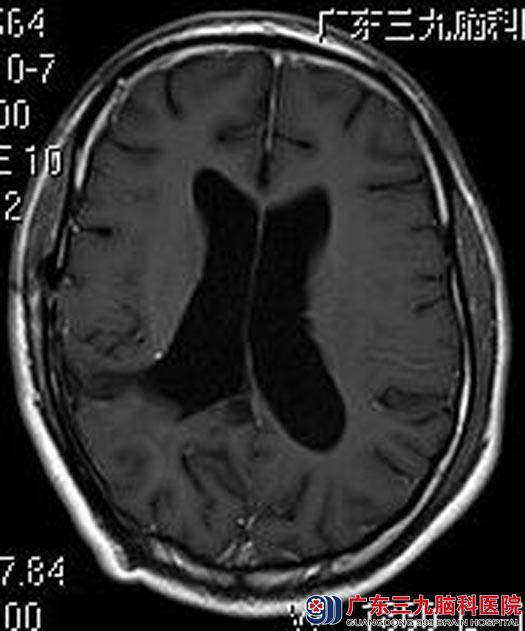

一年后,邱先生虽然没有不适症状,但觉得复查一下心里踏实点。回医院行头颅MR检查提示:未见明确肿瘤复发征象。

▲手术后